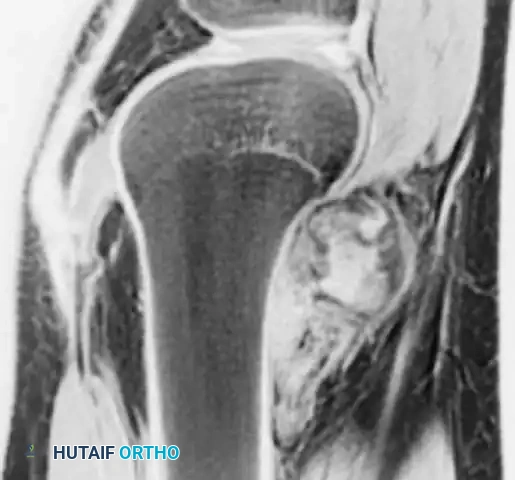

Image

Photograph of the resected distal femur specimen alongside the modular endoprosthetic implant prepared for reconstruction.